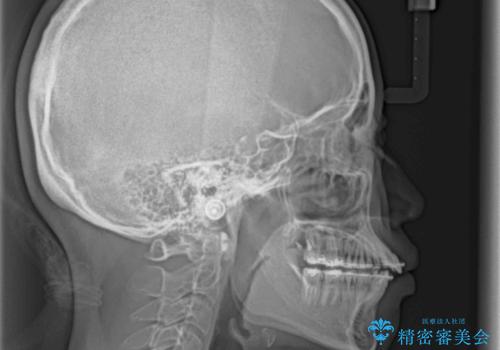

- 大学病院にて装置を装着したものの、治療が十分に受けることができないとのことで転院をされた患者様です。

上顎歯列が前方にあり、口元が閉じにくくなっていたため、既に装着されている装置を使用して上顎歯列全体を後方に移動させていくこととしました。